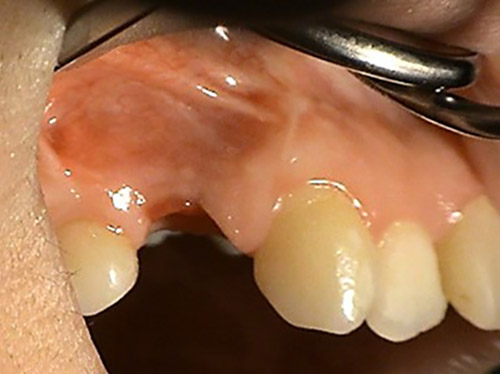

2. PHASE – state before making immediate impressions

3. PHASE – prosthetic fabrication of temporary crown on implant